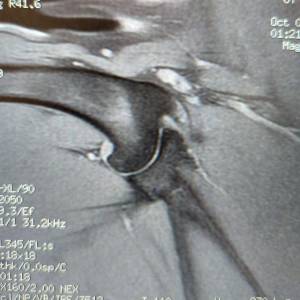

Main Gallery

Playing with a photo gallery function. It is possible to have multiple galleries, each within a namespace.